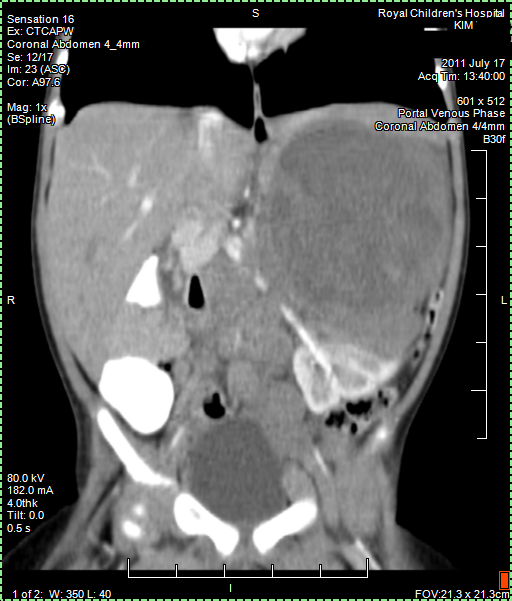

CT (CAT) scan 17July 2011